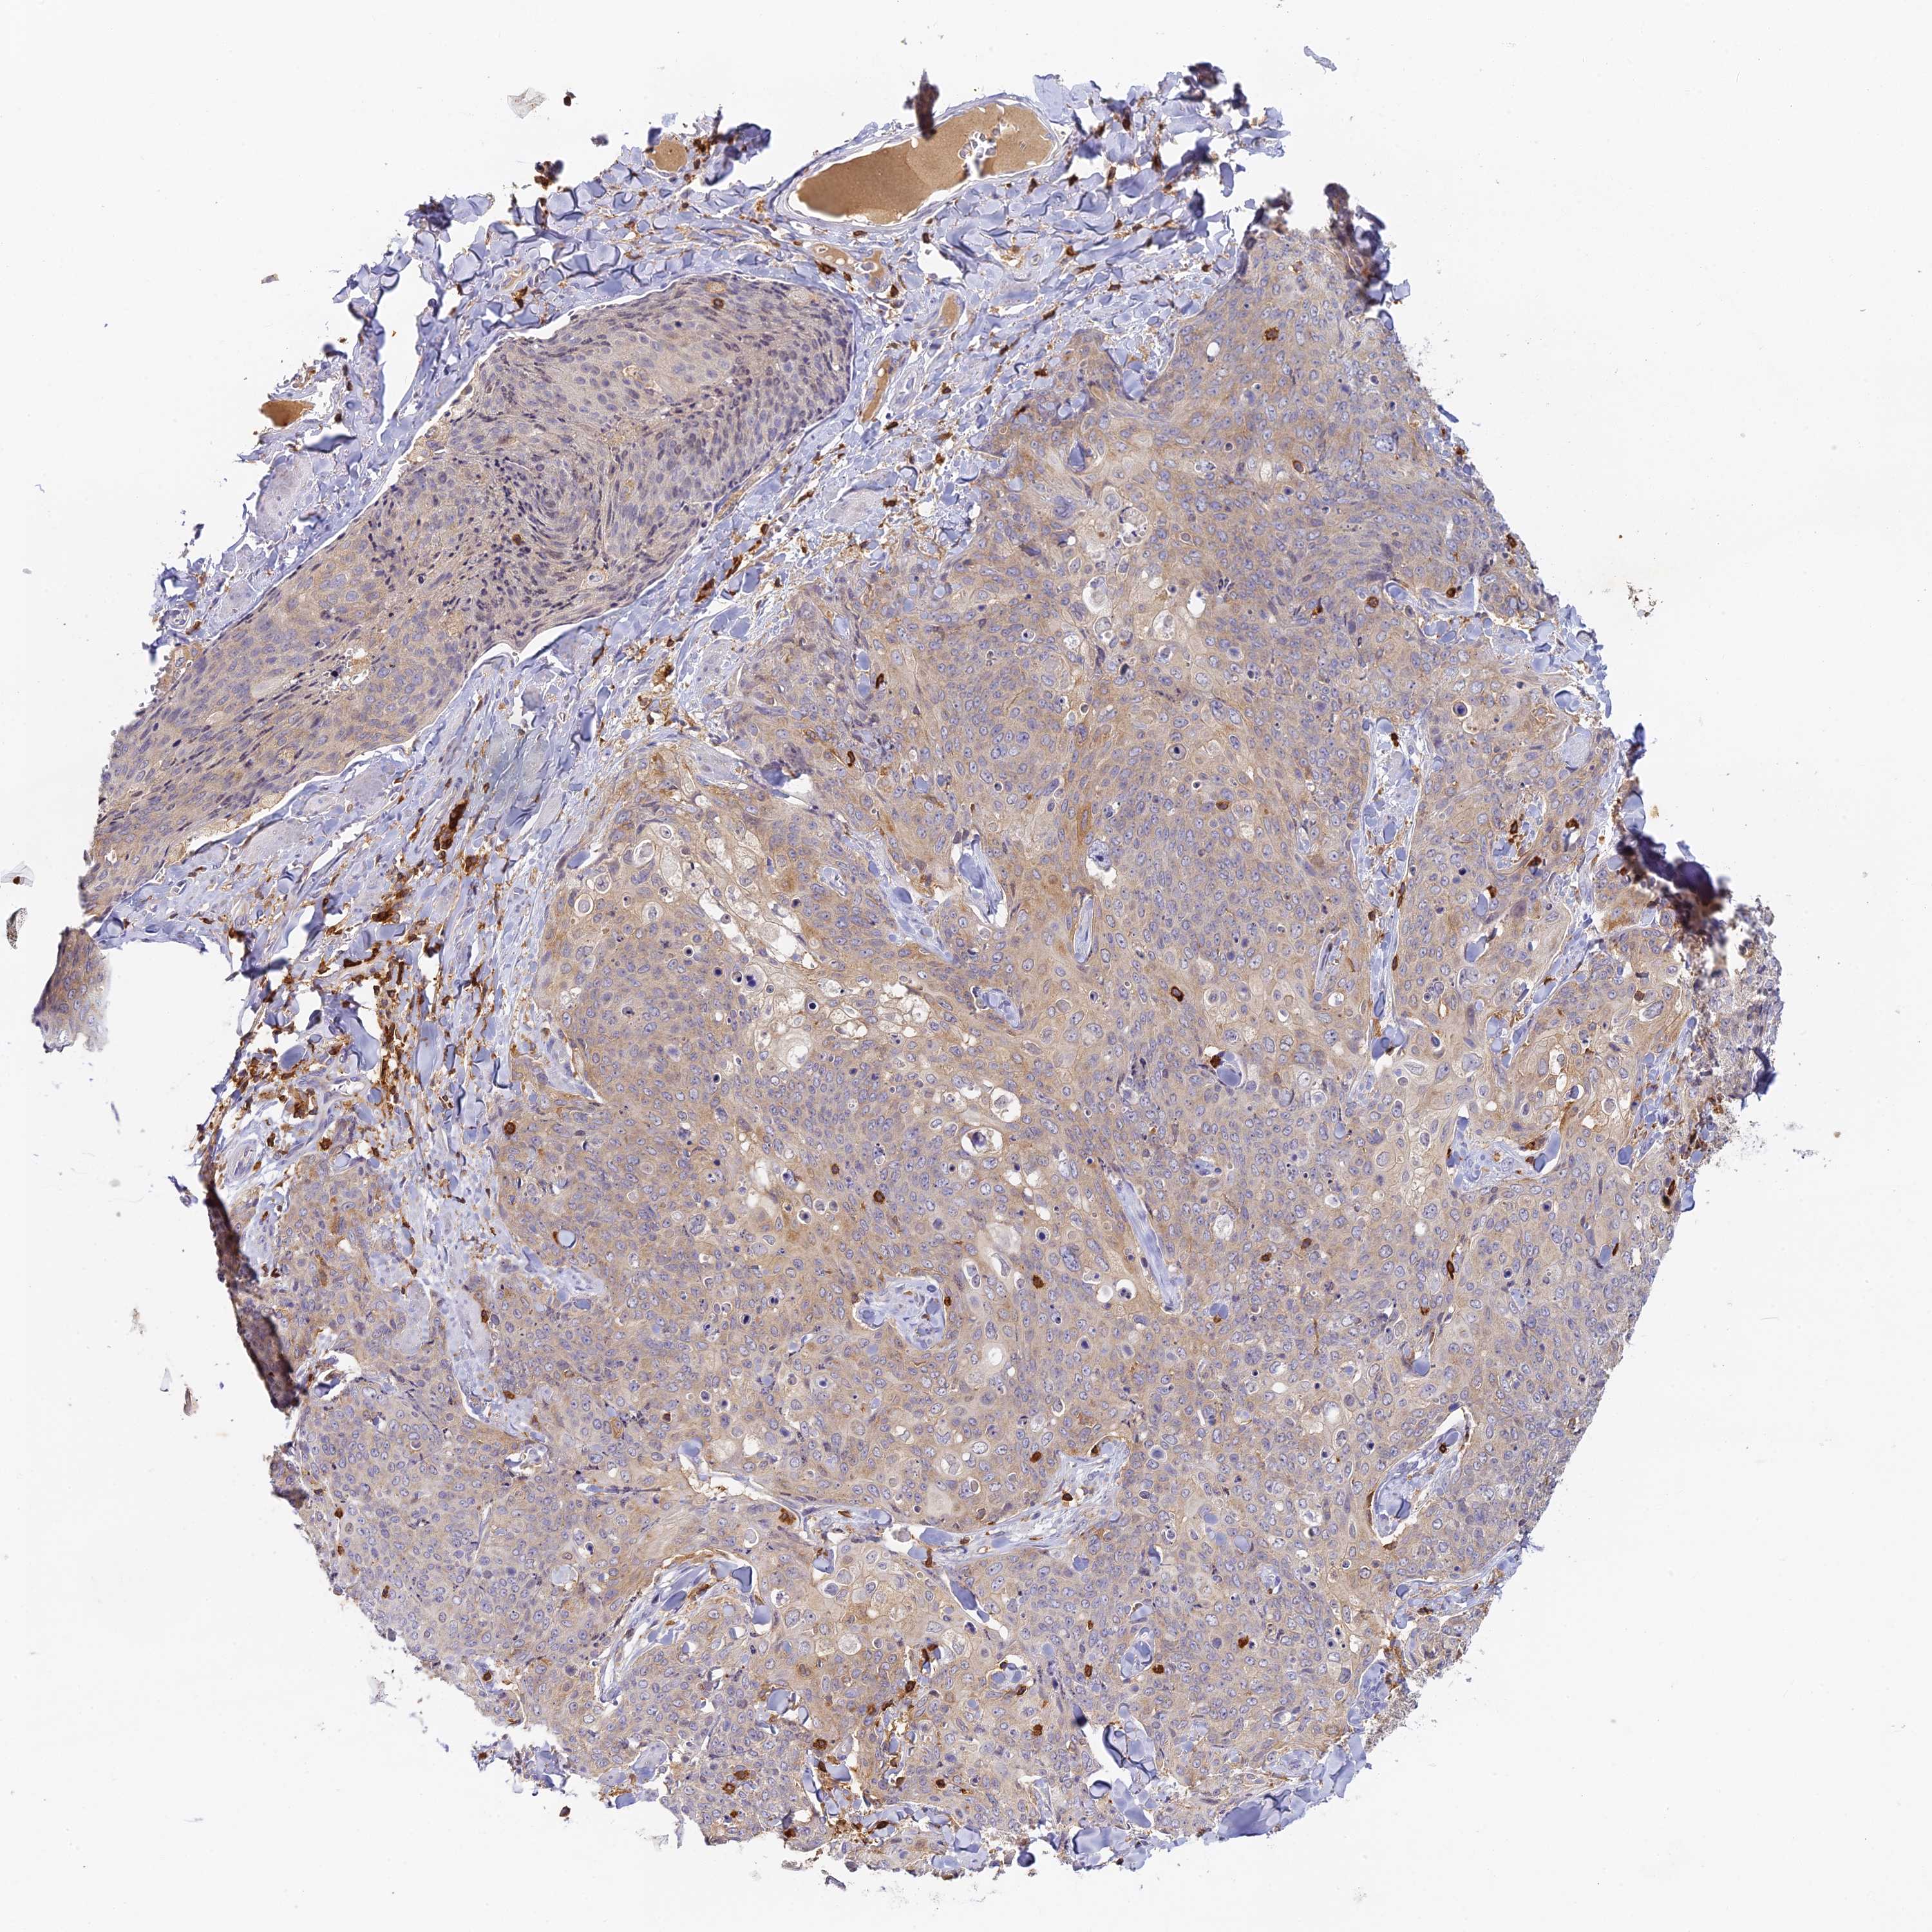

SKIN CANCER - Protein expressioni

A mouse-over function shows sample information and annotation data. Click on an image to view it in a full screen mode. Samples can be filtered based on level of antibody staining by selecting one or several of the following categories: high, medium, low and not detected. The assay and annotation is described here.

Each image is clickable and will lead to virtual microscopy that enables deeper exploration of all samples and also displays staining intensity scores, fraction scores and subcellular localization as well as patient and tissue information for each sample.

Antibody HPA067427

Staining

High

Medium

Low

Not detected

Intensity

Strong

Moderate

Weak

Negative

Quantity

>75%

75%-25%

<25%

None

Location

Nuclear

Cytoplasmic/membranous

Cytoplasmic/membranous,nuclear

Squamous cell carcinoma, NOS

Squamous cell carcinoma, metastatic, NOS